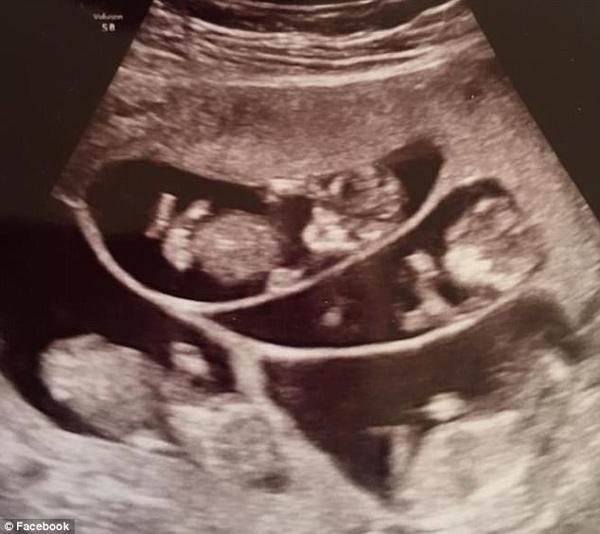

Chính vì vậy cô đã vô cùng choáng váng khi chỉ vài tuần sau khi dùng thuốc, các bác sĩ thông báo cô có tới 6 đứa con trong bụng.

“Đây là cú sốc lớn nhất trong cuộc đời tôi. Bác sĩ đã nhìn thấy tới 6 túi thai”, bà mẹ này chia sẻ với The Gadsden Times.

Tuy nhiên họ đã có cùng lúc 6 bào thai.